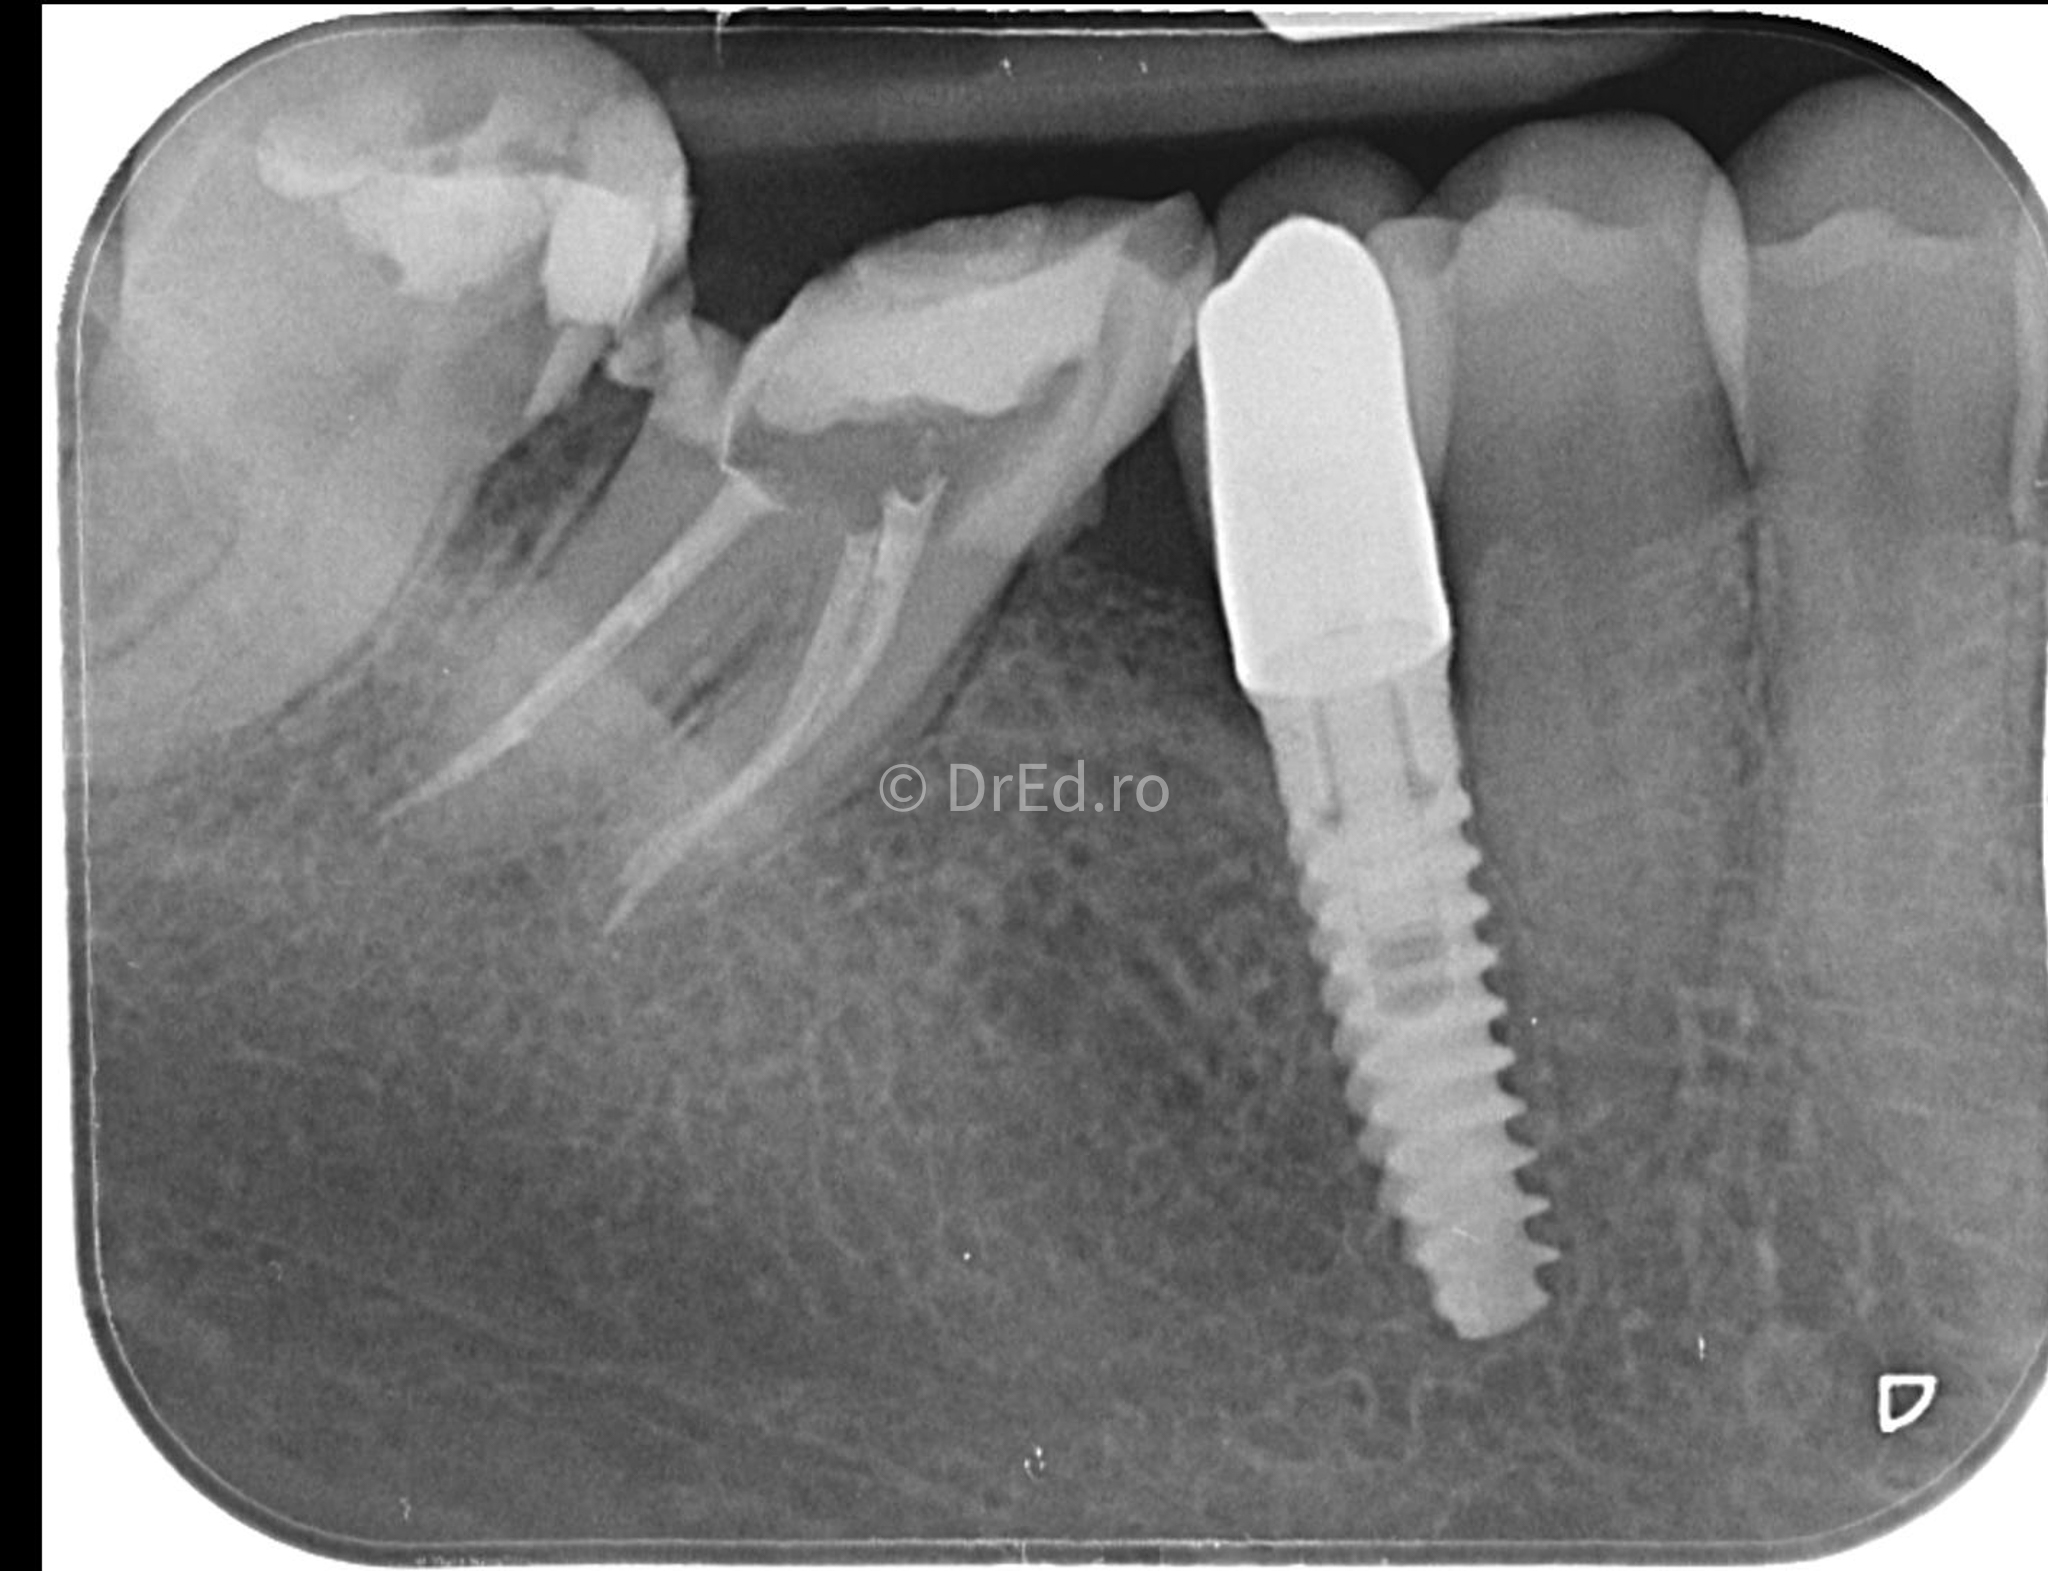

Galerie

Toate imaginile, fotografiile și radiografiile publicate pe acest site sunt protejate prin drepturi de autor și constituie proprietatea exclusivă a Dred.ro.

Aceste materiale sunt furnizate exclusiv în scop informativ și educațional și nu conțin date cu caracter personal sau informații care permit identificarea pacienților, în concordanță cu legislația privind protecția datelor cu caracter personal și GDPR.

Reproducerea, copierea, distribuirea, publicarea, transmiterea, modificarea sau orice altă utilizare, integrală ori parțială, a acestor materiale, în orice formă și prin orice mijloace, fără consimțământul prealabil scris al titularului drepturilor, este strict interzisă și poate atrage răspunderea civilă și/sau penală, în condițiile legii aplicabile privind drepturile de autor și protecția proprietății intelectuale.